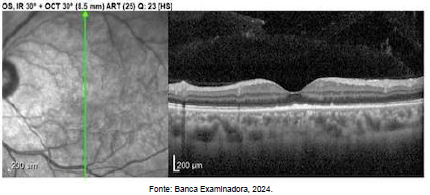

Paciente, sexo masculino, 20 anos, comparece ao servico de oftalmologia com queixa de baixa acuidade visual no olho esquerdo, com 3 dias de evolução. Nega sintomas associados. Paciente desconhece comorbidades prévias e nega uso de medicamentos. Ao exame, apresenta acuidade visual no OE 20/100 e presença de lesões sub-retinianas amarelo-pálidas. OD sem alterações ao exame. Imagens do OCT do paciente abaixo.